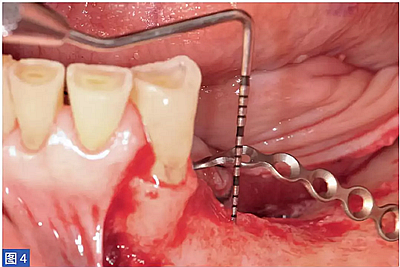

在整個手術(shù)過程中以及術(shù)后12 個月都要評估并發(fā)癥的發(fā)生。在術(shù)后12 個月,患者都要通過視覺模擬量表(VAS)對手術(shù)的滿意度從0(非常不滿意)到10(非常滿意)進行評估。這些問題針對對于治療過程的主觀評價。圖1-12 顯示了兩個典型病例的手術(shù)。

圖4:病例1. 術(shù)中內(nèi)固定鈦板。